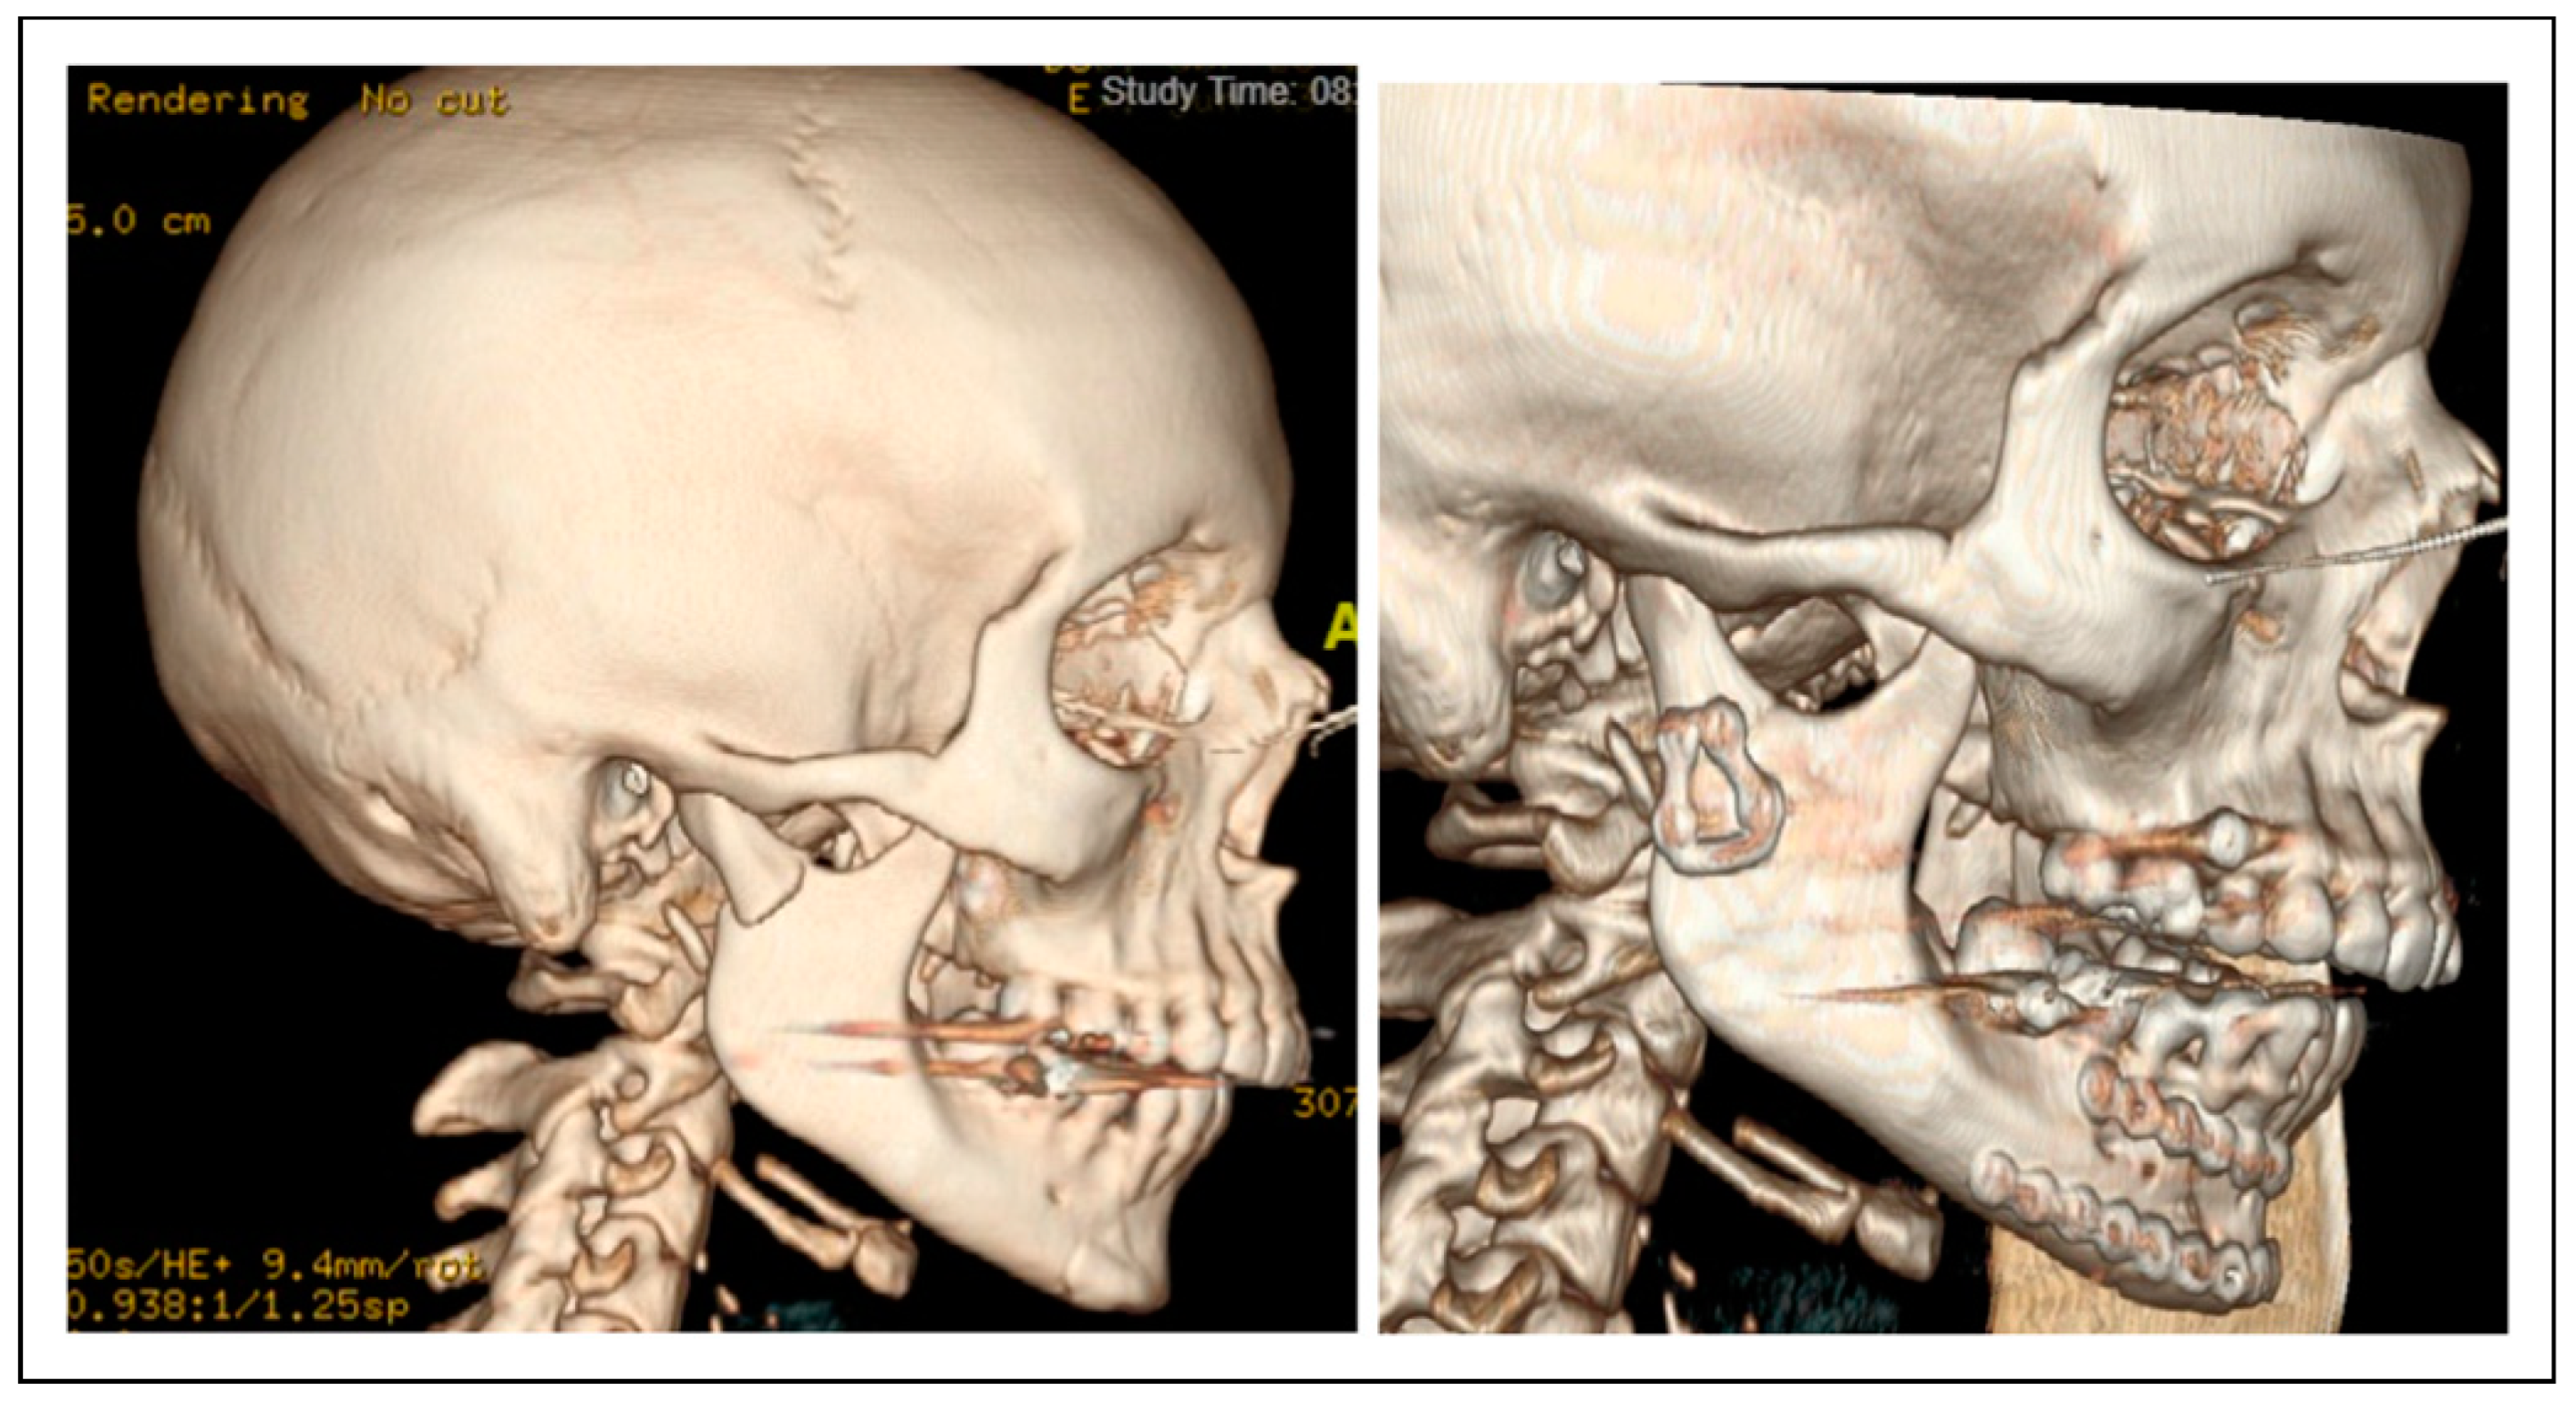

Clinical Experience with a Less Invasive Surgical Transparotid Approach and Trapezoidal Plate for Neck and Base Condylar Fractures: A Retrospective Study

Patients and Methods